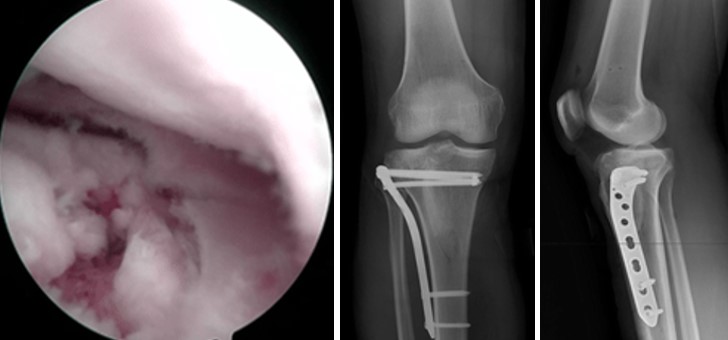

Артроскопічно - асистовані операції дозволяють мінімізувати травматичність втручання, здійснити точну репозицію суглобової поверхні під візуальним контролем, діагностувати та лікувати супутні внутрішньосуглобові пошкодження м’яких тканин: менісків та зв'язок.

Відкрита репозиція та внутрішня фіксація залишається золотим стандартом лікування. Використовують різні хірургічні доступи залежно від локалізації перелому. Фіксацію здійснюють кутовими пластинами з кутовою стабільністю, гвинтами, спонгіозними гвинтами з шайбами. При наявності кісткового дефекту виконують кісткову пластику.

Показання до операції: зміщення суглобової поверхні більше 2-3 мм, нестабільність колінного суглоба, відкриті переломи, пошкодження судинно-нервових структур, пошкодження внутрішньосуглобових структур: меніски та зв’язки.